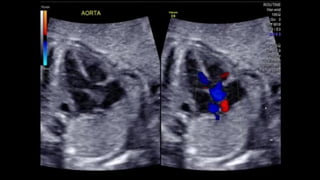

• This still frame image

of a parasternal short

axis view of the

echocardiogram of a

patient with tetralogy

of Fallot demonstrates

the antero-cephalad

deviation of the outlet

septum into the right

ventricular outflow

tract.

• A slightly modified view (a), angled to optimize

imaging of the pulmonary arteries in the patient

imaged to produce Figure 6, reveals significant

hypoplasia of the pulmonary trunk and the

pulmonary arteries, which result from the antero-

cephalad deviation of the outlet septum. The

pulmonary valvar leaflets are not visualized. In panel

b, colour Doppler has been used, and demonstrates

turbulence and acceleration of the flow of blood in

the right ventricular outflow tract, originating at the

level of the deviated outlet septum. The turbulence

continues into the hypoplastic pulmonary trunk and

pulmonary arteries.